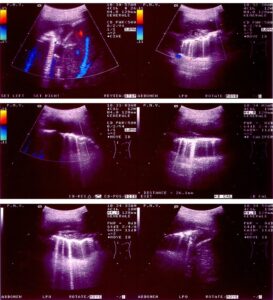

La crescita ridotta nei primi tre mesi di gravidanza e' un fattore di rischio cardiovascolare per l'infanzia, secondo un nuovo...